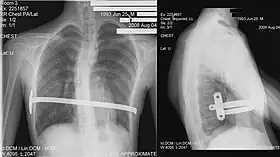

Pectus excavatum on PA chest radiograph with shift of heart shadow to the left and radioopacity of the right paracardiac lung field

Chest x-rays are also useful in the diagnosis. The chest x-ray in pectus excavatum can show an opacity in the right lung area that can be mistaken for an infiltrate (such as that seen with pneumonia).[20] Some studies also suggest that the Haller index can be calculated based on chest x-ray as opposed to CT scanning in individuals who have no limitation in their function.[21]